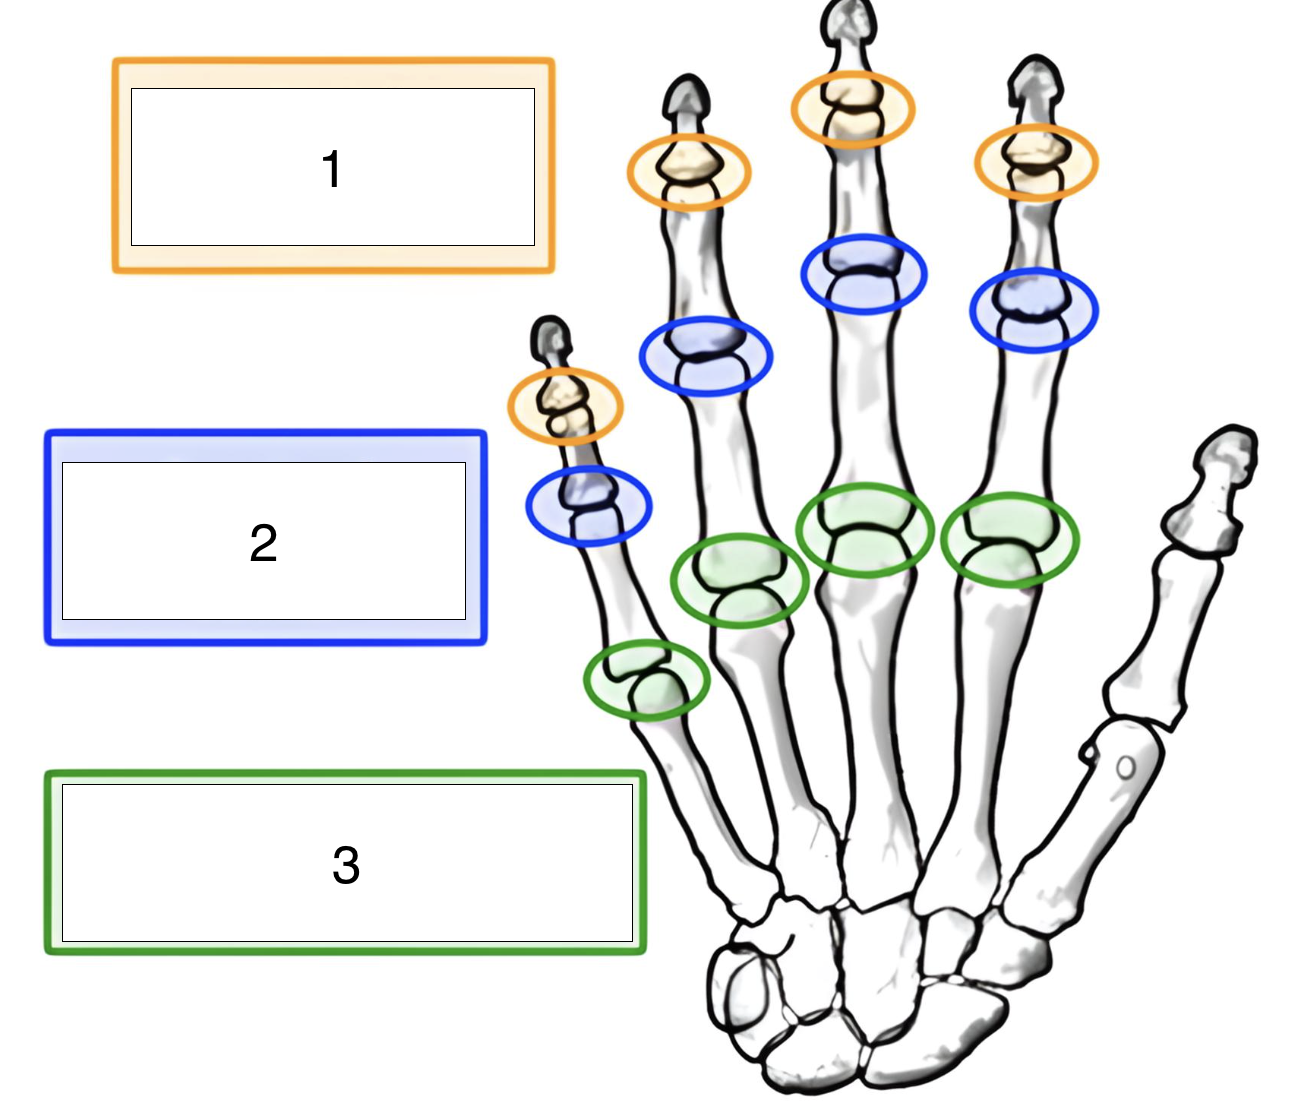

what is the highlighted joint (green, 3)?

metacarpophalangeal (MCP)

what is the highlighted joint (blue, 2)?

proximal interphalangeal (PIP)

what is the highlighted joint (orange, 1)?

distal interphalangeal (DIP)